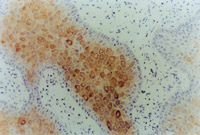

原位切取創(chuàng)面組織病理切片檢查,見(jiàn)壞死上皮組織間有大量顆粒樣組織,新生上皮細(xì)胞和膠原纖維組織呈團(tuán)樣增生,并可見(jiàn)到典型的類似于胎兒皮膚結(jié)構(gòu)的皮膚胚胎基(embryonic base,EB)(圖5-3-4a,5-3-4b)。MEBT治療10天后,在創(chuàng)面邊緣取上皮組織病理切片可見(jiàn)到較原始的上皮組織。

5-3-4a 新生上皮組織和膠原纖維增生,可見(jiàn)典型EB(皮膚胚胎基) HE×40

5-3-4b 新生上皮組織中可見(jiàn)微血管,膠原纖維和上皮細(xì)胞(干細(xì)胞)形成的皮膚胚胎基組織  HE×40